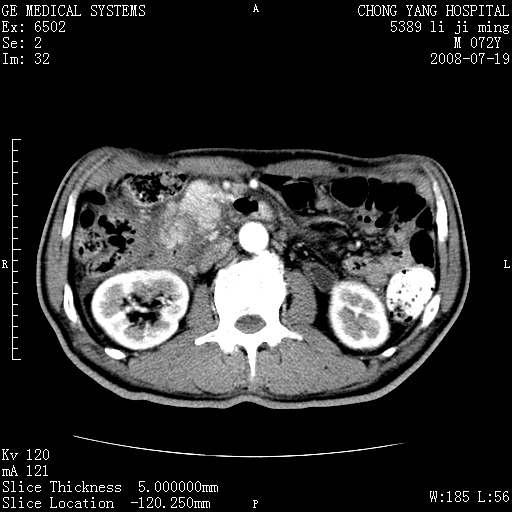

以下是引用zjzjr在2008-7-19 20:57:00的发言:[br]胰头增大,边缘模糊,周围可见渗出影,右侧肾前筋膜增厚.支持胰腺炎.

以下是引用yangyudong333在2008-7-20 6:56:00的发言:[br]胰腺增大尤以胰头明显,边缘模糊,周围可见渗出影,右侧肾前筋膜增厚,肠管於涨.支持胰腺炎

以下是引用不学无术在2008-7-19 23:15:00的发言:[br]胰腺增大尤以胰头明显,边缘模糊,周围可见渗出影,右侧肾前筋膜增厚,肠管於涨.支持胰腺炎